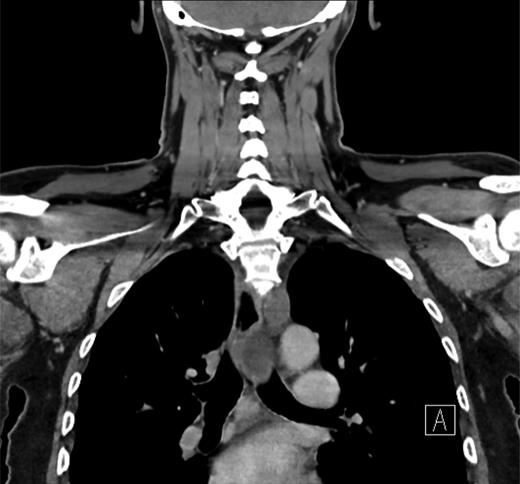

Thyroid function tests were normal. He underwent a computed tomographic (CT) scan of the neck and chest (Figs 1–3). It showed a large multinodular goitre with retrosternal extension of the left lobe to the arch of the aorta. The trachea was deviated to the right. Paraoesophageal swellings were noted in the upper posterior mediastinum, the largest of which measured 2 cm. These were non-enhancing masses, with no evidence of haemorrhage. The case was reviewed in a multidisciplinary meeting to exclude the differential diagnosis of necrotic paraoesphageal lymph nodes. The oesophagus was unremarkable, with no thickening or air-fluid level. In view of this and the continuity of the swellings with the thoracic duct, no further investigation or biopsy was undertaken.

Sagittal CT image showing a thyroid goitre with retrosternal extension and paraoesophageal swellings.